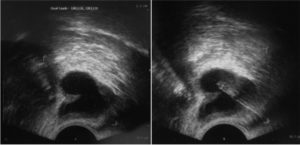

- УЗИ мошонки позволяет поставить диагноз сперматоцеле с наибольшей точностью.

Пи кистах семявыбрасывающего протока при ультразвуковом обследовании видно расширение семенного пузырька на стороне поражения.

При выполнении ультразвуковой диагностики трансректальным доступом лучше видны кисты с диаметром больше 10 мм, при обычном, трансабдоминальном исследовании, маленькие образования диагностировать невозможно.